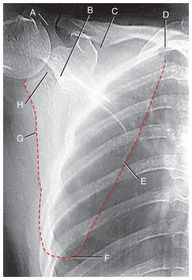

A. axilla B. lateral (axillary) border C. scapulohumeral joint (glenohumeral) D. superior border E. medial border